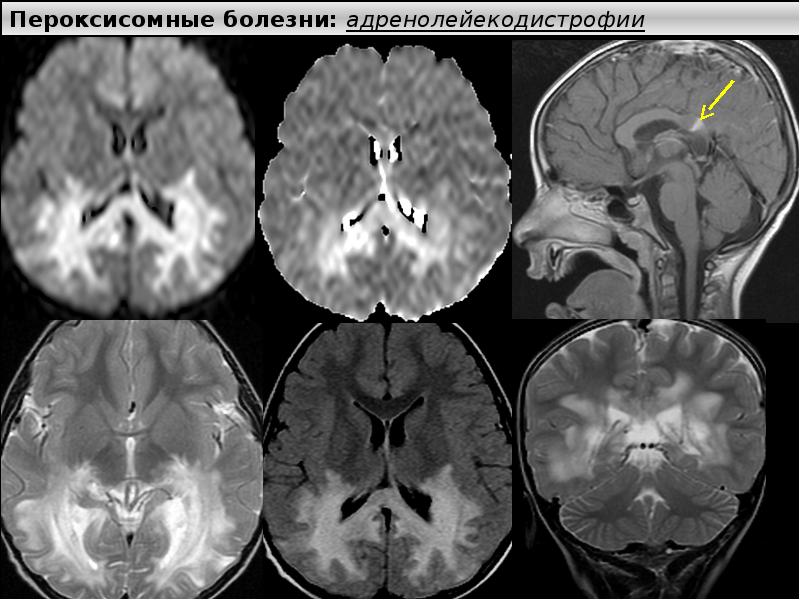

Иллюстрации и пояснения: гиподенсивный очаг на КТ головного мозга